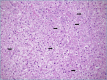

Non-alcoholic fatty liver disease (NAFLD) encompasses a spectrum of different conditions which are characterized by hepatic steatosis in the absence of secondary causes. It is currently the most common chronic liver disease worldwide, and its estimated prevalence is about 1.5-6.5%. The only histological finding of steatosis ("simple" steatosis) represents the uncomplicated form of NAFLD, while non-alcoholic steatohepatitis (NASH) is its inflammatory subtype associated with disease progression to cirrhosis and hepatocellular carcinoma (HCC), and represents the major indication for liver transplantation. NASH is still a diagnostic and therapeutic challenge for clinicians and liver biopsy is currently the only accepted method to reliably distinguish NASH from "simple" steatosis. From the histological perspectives, NAFLD and NASH continue to be an area of active interest for pathologists, with a specific focus on better methods of evaluation, morphologic clues to pathogenesis, and predictors of fibrosis progression. This review focuses on histopathology of NAFLD in adults, with the aim to provide a practical diagnostic approach useful in the clinical routine.